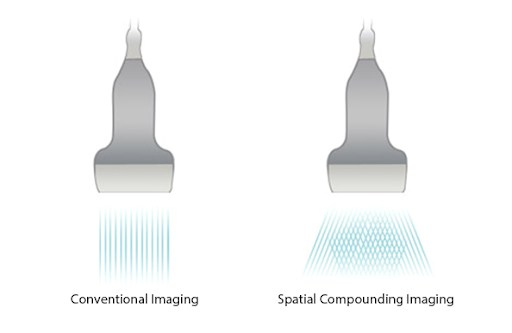

- IBiem Многолучевое сканирование для повышения четкости границ тканей.

iBeam (визуализация с частичным компаундингом

Позволяет использовать несколько углов сканирования для формирования единого изображения, что приводит к увеличению контрастного разрешения и улучшению визуализации.